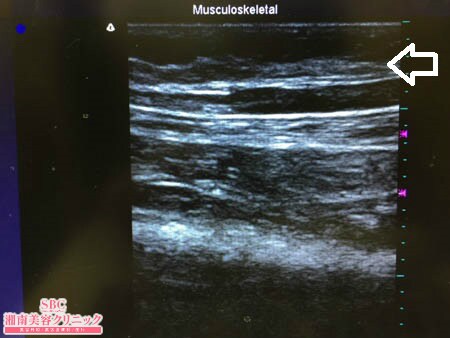

No.181921【脂肪吸引】【動画あり】湘南美容外科脂肪吸引最高責任者である竹田先生による脂肪吸引のフォトギャラリー!細くなりたいんです!という患者様に対する太ももの脂肪吸引!術中3Dタッチビュー・左太もも前面

いつものように3Dタッチビュー(超音波)で

皮下脂肪層を評価してみましょう。

上記の画像通りの結果です。